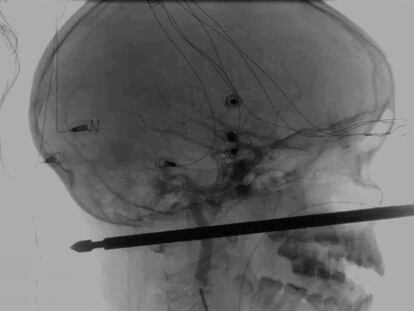

El utensilio le entró por la mejilla a la altura de la nariz y le salió por la nuca, pero no le tocó los ojos, ni la médula espinal ni ningún vaso sanguíneo